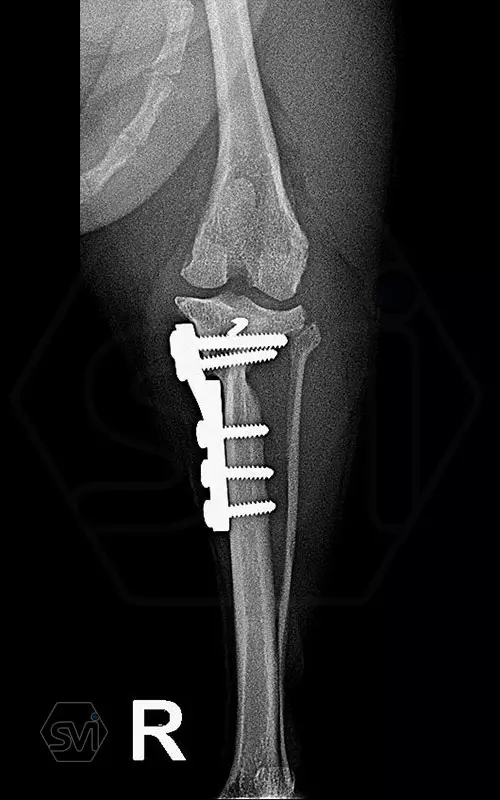

Introducing the TPLO-M „terraced” plate family from Smartvetimplants.com

In small dogs, medial patella luxation (MPL) and the rupture of anterior cruciate ligament (RACL) often occur simultaneously. During the surgical procedure, the joint must be stabilized and the patella fixed in the middle axis at the same time.

The solution of Smatvetimplants is the TPLO-M plate family with terrace:

Small TPLO-M plate:

part of a polyaxial locking system, symmetrical, available with 2.5 and 4.0mm terraces, torx-head, 2.4mm locking screws (2.0 and 2.4mm AO screws can also be inserted), material steel. Optimized for R12 and R15 blades.

Between October 2020 and December 2021, we performed 19 TPLO-M surgeries at the Animal Hospital in Nyíregyháza,: 16 times used the mini (2.0 R12) and 3 times the small (2,4 R15) TPLO-M plate.

The experience is very encouraging, we find the system and plates suitable for the simultaneous treatment of MPL and RACL. ( in case of 4/4 pat. lux. also). We will back soon with details.